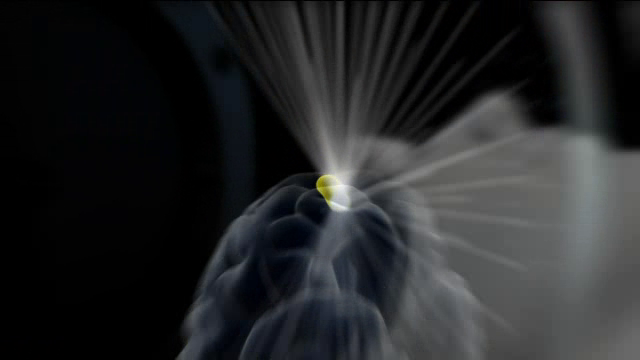

Ως ακτινοχειρουργική ορίζεται η χρήση ιονισμένης ακτινοβολίας (ακτίνες γάμμα) για την καταστροφή χωροκατακτητικών εξεργασιών του εγκεφάλου με μεγάλη ακρίβεια (στερεοτακτικά) και χωρίς να απαιτείται διάνοιξη του κρανίου. Η επέμβαση πραγματοποιείται με το πλήρως αυτοματοποιημένο σύστημα γ-knife, στο οποίο περίπου 200 πηγές ακτινοβολίας συγκλίνουν τη δράση τους σε ένα ή περισσότερους προκαθορισμένους στόχους στον εγκέφαλο προκαλώντας τους συγκεντρωμένη ακτινική βλάβη, χωρίς να τραυματίζουν τον υγιή ιστό κατά την πορεία τους. Η μέθοδος είναι κατάλληλη για μικρές έως μεσαίες σε μέγεθος χωροκατακτητικές εξεργασίες του εγκεφάλου και της βάσης του κρανίου, όπως οι μεταστατικοί όγκοι, τα μηνιγγιώματα, τα ακουστικά νευρινώματα, οι αρτηριοφλεβώδεις δυσπλασίες, κ.α. Η θεραπεία γ-knife είναι επίσης κατάλληλη για ορισμένες περιπτώσεις λειτουργικής νευροχειρουργικής όπως η νευραλγία του τριδύμου. Η επέμβαση γίνεται σε μία συνεδρία κατά κανόνα και ο χρόνος νοσηλείας είναι μερικές ώρες έως 1 ημέρα.

Περιγραφή της θεραπείας Η θεραπεία με γ-knife πραγματοποιείται κατά κανόνα σε μία συνεδρία. Το πρωί της θεραπείας στερεώνεται στο κεφάλι του ασθενούς ένα τετράγωνο μεταλλικό πλαίσιο από τιτάνιο. Η στερέωση γίνεται με τέσσερεις καρφίδες οι οποίες τοποθετούνται υπό τοπική αναισθησία. Ο ασθενής υποβάλλεται σε μαγνητική ή/και αξονική τομογραφία εγκεφάλου (και ψηφιακή αγγειογραφία στις αρτηριοφλεβώδεις δυσπλασίες) με το μεταλλικό πλαίσιο. Ακολουθεί ο σχεδιασμός της θεραπείας σε εξειδικευμένο σύστημα υπολογιστών με την συμμετοχή και έγκριση ακτινοθεραπευτή και ακτινοφυσικού. Το πλάνο θεραπείας εξάγεται ηλεκτρονικά στο ρομποτικό σύστημα γ-knife και ο ασθενής τοποθετείται στο μηχάνημα. Η κεφαλή του ασθενούς παραμένει ακινητοποιημένη κατά την διάρκεια της θεραπείας (το μεταλλικό πλαίσιο εφαρμόζει σε ειδική υποδοχή). Η θεραπεία είναι αθόρυβη, ο ασθενής δεν αντιλαμβάνεται τίποτα από αυτήν και διαρκεί από 30 λεπτά έως μερικές ώρες. Μετά το πέρας της θεραπείας αφαιρείται το μεταλλικό πλαίσιο από το κεφάλι του ασθενούς, ο οποίος παραμένει στο νοσοκομείο μερικές ώρες έως και 1 ημέρα. |